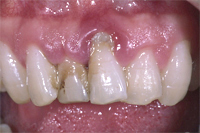

Ein seitlicher Oberkieferschneidezahn ist als sogenannter Zapfenzahn (angeboren) in die Mundhöhle durchgebrochen (Abb. 1). Nach orthodontischer Zahnbehandlung haben wir dem 16 Jahre alten Mädchen den Vorschlag gemacht, mittels zwei adhäsiv gelegten Kompositfüllungen und ohne Beschleifen den Zapfenzahn in einen natürlichen Schneidezahn umzuformen (Abb. 2).

Ein 9-jähriges Mädchen kam eine Stunde nach einem Sturz, bei welchem es den linken oberen mittleren Schneidezahn komplett herausgeschlagen und den rechten massiv traumatisiert hatte (wackelte sehr stark), in unser Praxis (Röntgenbild Abb. 3). Der herausgeschlagene Zahn wurde sofort replantiert und beide mittleren Schneidezähne in die ursprüngliche Lage zurückversetzt und in dieser Situation mittels eines Drahtbogens an die Nachbarzähne fixiert (Röntgenbild Abb. 4).

Die verletzten Schneidezähne mussten beide wurzelbehandelt werden (Röntgenbild Abb. 5, siehe auch Kapitel Endodontie).

Einen Monat später haben wir beide Zähne intern gebleicht und dann die abgebrochenen Zähne wieder aufgebaut (Abb. 6 und 7).